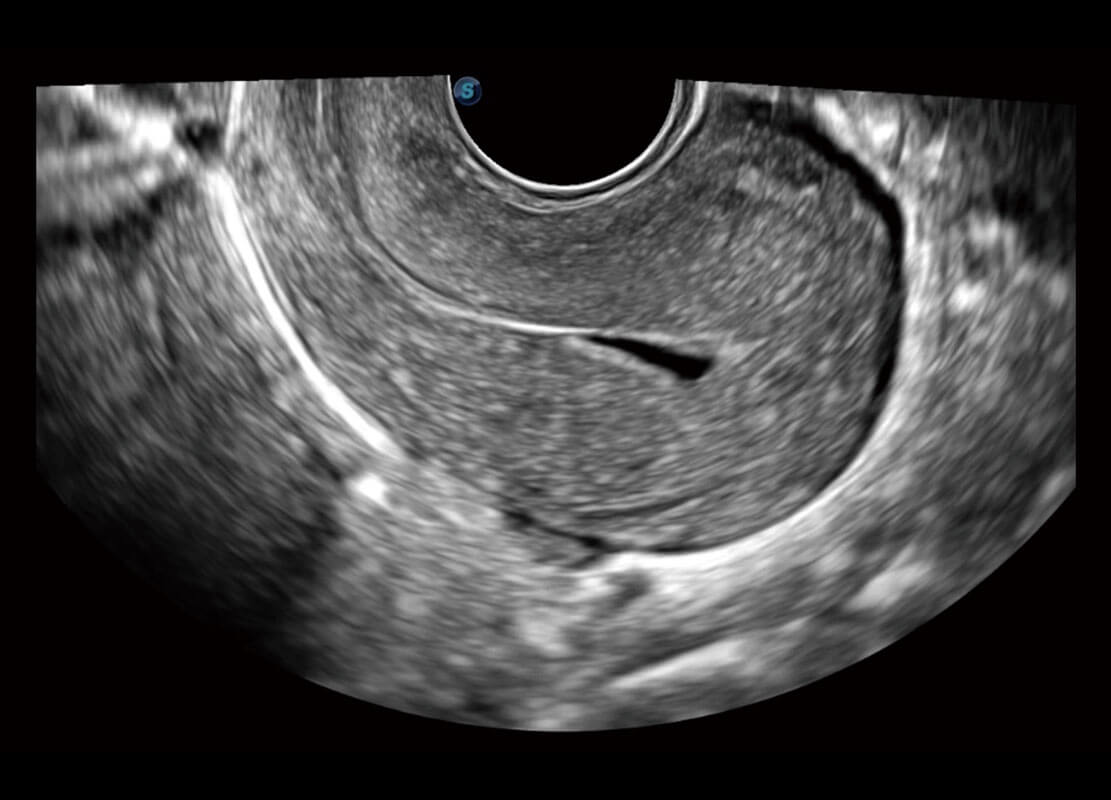

• 腔内妇科-宫腔分离

• 腔内妇科-卵巢

• 腔内三维-宫内节育器

• 腔内三维-光影成像